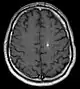

Cerebral cavernous malformation (CCM)

Developmental venous abnormality seen on a (T1 axial contrast enhanced) MRI.

Diagnosis is generally made by magnetic resonance imaging (MRI), particularly using a specific imaging technique known as a gradient-echo sequence MRI, which can unmask small or punctate lesions that may otherwise remain undetected. These lesions are also more conspicuous on FLAIR imaging compared to standard T2 weighing. FLAIR imaging is different from gradient sequences. Rather, it is similar to T2 weighing but suppresses free-flowing fluid signal. Sometimes quiescent CCMs can be revealed as incidental findings during MRI exams ordered for other reasons. Many cavernous hemangiomas are detected "accidentally" during MRIs searching for other pathologies. These "incidentalomas" are generally asymptomatic. In the case of hemorrhage, however, a CT scan is more efficient at showing new blood than an MRI, and when brain hemorrhage is suspected, a CT scan may be ordered first, followed by an MRI to confirm the type of lesion that has bled.[19] Sometimes the lesion appearance imaged by MRI remains inconclusive. Consequently, neurosurgeons will order a cerebral angiogram or magnetic resonance angiogram. Since CCMs are low flow lesions (they are hooked into the venous side of the circulatory system), they will be angiographically occult (invisible). If a lesion is discernible via angiogram in the same location as in the MRI, then an arteriovenous malformation (AVM) becomes the primary concern.